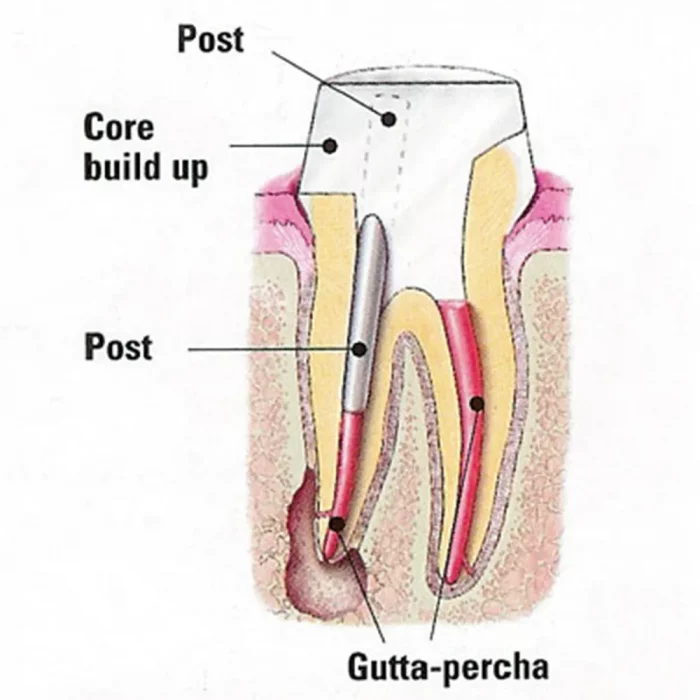

Tenax Fiber Trans is an excellent alternative to metal posts if highly esthetic, metal-free restorations are desired.

Fiber posts with high strength, high bending strength, and resistance to shearing force have an elastic modulus similar to that of dentin. It can absorb bite force and external forces to avoid root features. 4% taper in the bottom third. It is translucent hence light can pass through it while using a light cure.

- Prepare the post space using specific drills

- Trial fit the Fiber posts and determine the desired length.

- After etching and rinsing the canal and super-structure, place the adhesive on the tooth.

- Place the dual cure resin cement and core build-up material.

- Final preparations. Note that the posts has to be placed over the centric cusps.